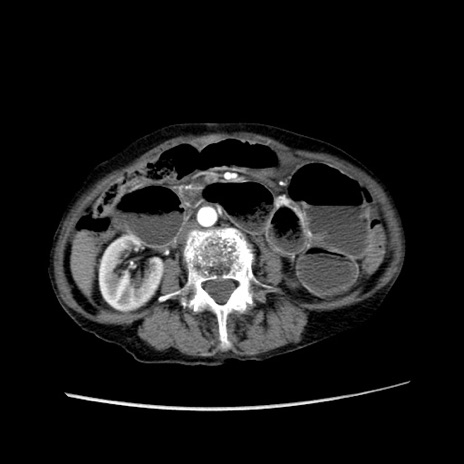

冠状断像

【症例】80歳代女性

【主訴】胸のつかえ感

【現病歴】約9時間前に食後から胸のつかえた感じあり、嘔吐あり、来院。

【既往歴】胃癌(全摘)、胆摘、虫垂炎

【身体所見】心窩部に圧痛あり、反跳痛なし。

【データ】WBC 5700、CRP 0.05